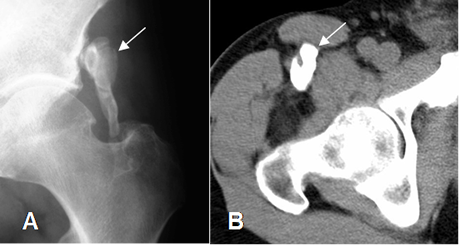

Las calcificaciones aparecen entre las 6 y 8 semanas después de la lesión inicial (6) y se pueden identificar en Rx o TAC como imágenes densas, rodeadas por un halo radiolúcido y paralelas al eje del hueso (2, 3). (Fig 30).

Fig 30. Miositis osificante.

A: Rx AP y B: TAC axial. 2 casos diferentes donde existe calcificación de tejidos blandos en relación con los grupos musculares, por miositis osificante.